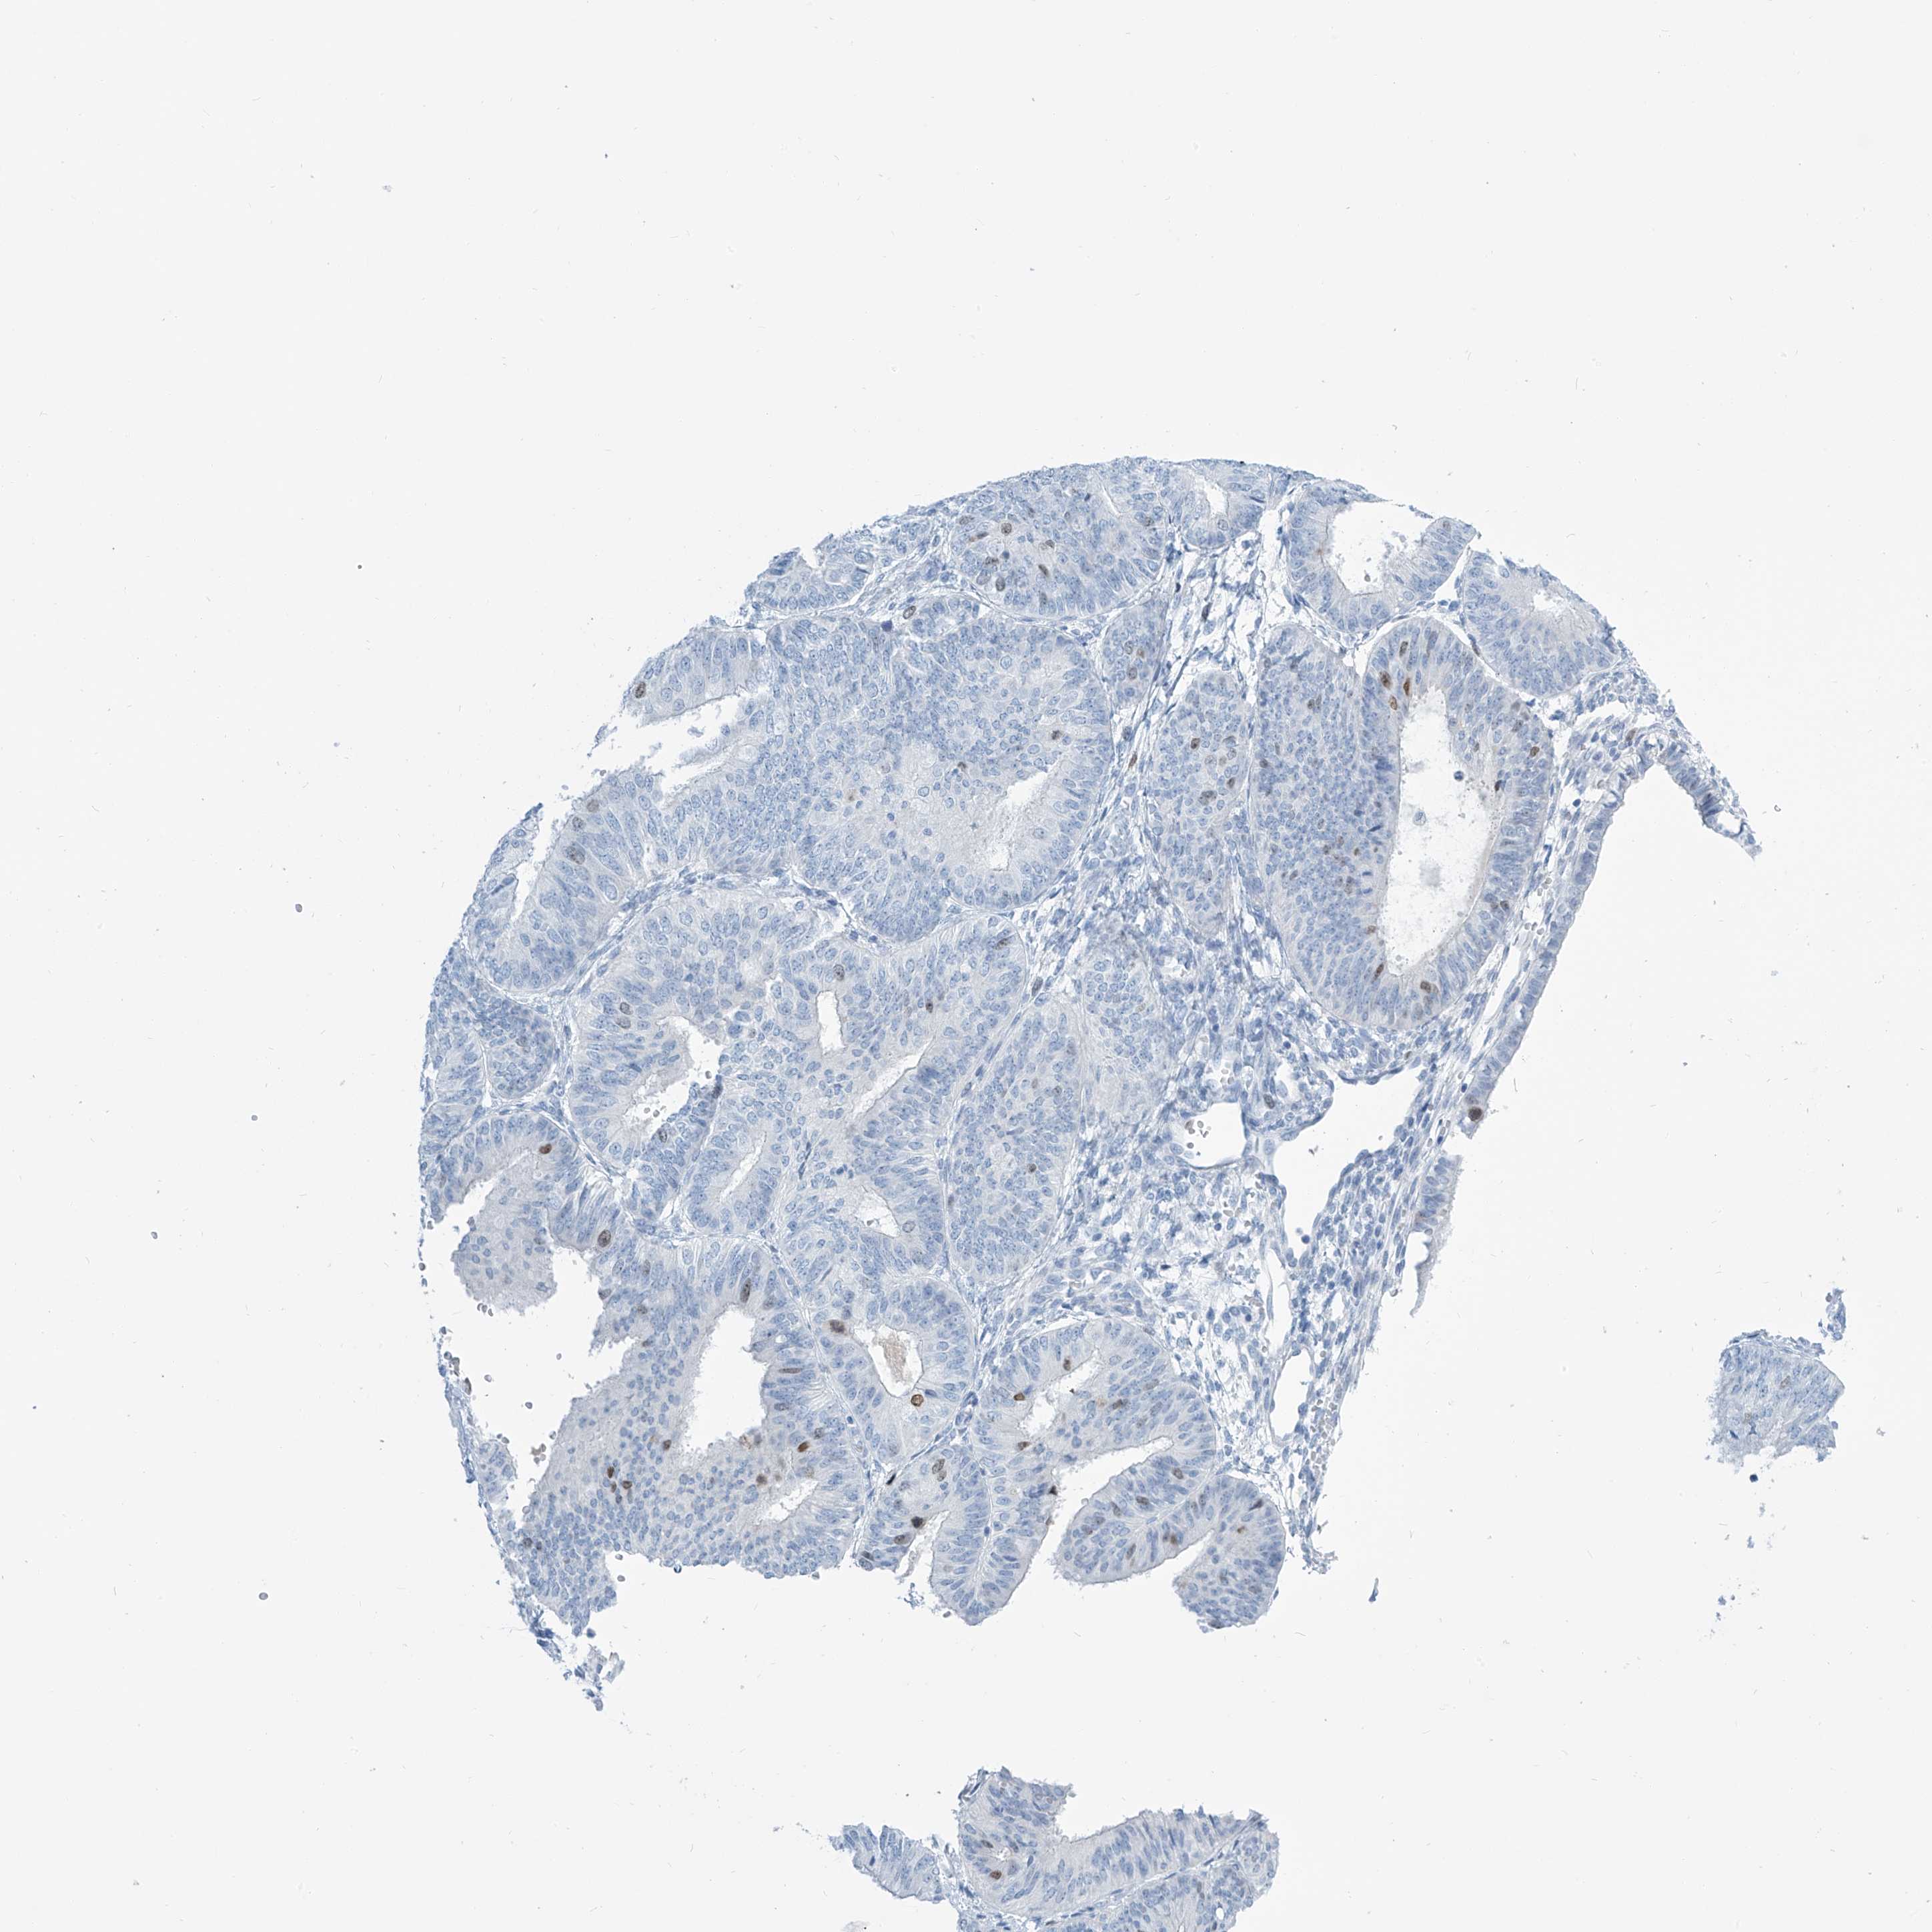

ENDOMETRIAL CANCER - Protein expressioni

A mouse-over function shows sample information and annotation data. Click on an image to view it in a full screen mode. Samples can be filtered based on level of antibody staining by selecting one or several of the following categories: high, medium, low and not detected. The assay and annotation is described here.

Note that samples used for immunohistochemistry by the Human Protein Atlas do not correspond to samples in the TCGA dataset.

Antibody stainingi

Antibody staining in the annotated cell types in the current human tissue is reported as not detected, low, medium, or high, based on conventional immunohistochemistry profiling in selected tissues. This score is based on the combination of the staining intensity and fraction of stained cells.

Each image is clickable and will lead to virtual microscopy that enables deeper exploration of all samples and also displays staining intensity scores, fraction scores and subcellular localization as well as patient and tissue information for each sample.

Antibody HPA035163

Staining

High

Medium

Low

Not detected

Intensity

Strong

Moderate

Weak

Negative

Quantity

>75%

75%-25%

<25%

None

Location

Nuclear

Cytoplasmic/membranous

Cytoplasmic/membranous,nuclear

Adenocarcinoma, NOS

Adenocarcinoma, metastatic, NOS